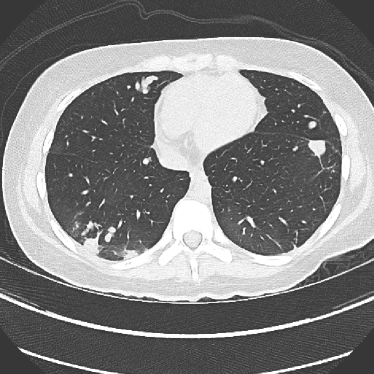

Refer to caption(a) Clinical Standard IRRefer to caption(a) Clinical Standard IR

Refer to caption(b) JENGRefer to caption(b) JENG

Refer to caption(c) Clinical Standard IRRefer to caption(c) Clinical Standard IR

Refer to caption(d) JENGRefer to caption(d) JENG

Figure 14: Qualitative clinical results from a thoracic CT staging dataset for a 12-year-old with osteosarcoma with pulmonary metastases. The clinical standard hybrid IR is shown on the left and JENG is on the right. (a) The clinical standard hybrid IR in lung window with a window center of -600 HU and a window width of 1500 HU. (b) JENG at a resolution comparable to the clinical standard, but with less noise and fewer artifacts. (c) The clinical standard hybrid IR in soft tissue window with a window center of 55 HU and a window width of 440 HU. A metastatic lung cancer nodule can be found in the left upper lobe. (d) JENG in soft tissue window at a comparable resolution, but with less noise and fewer artifacts. Note that JENG is not fully corrected for beam hardening artifacts.